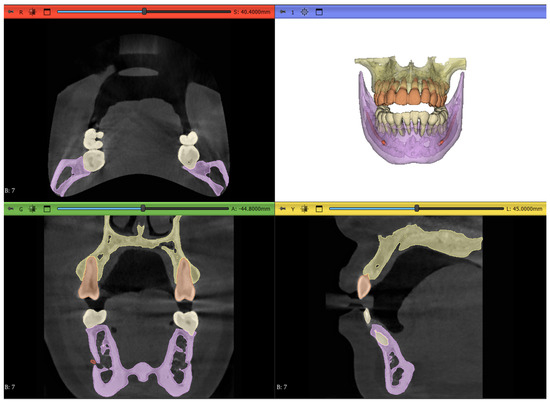

2.7. Workflow 4: Automated DentalSegmentator

- Maxilla and upper skull

- Mandible

- Upper teeth

- Lower teeth

- Mandibular canal

2.8. Post-Processing